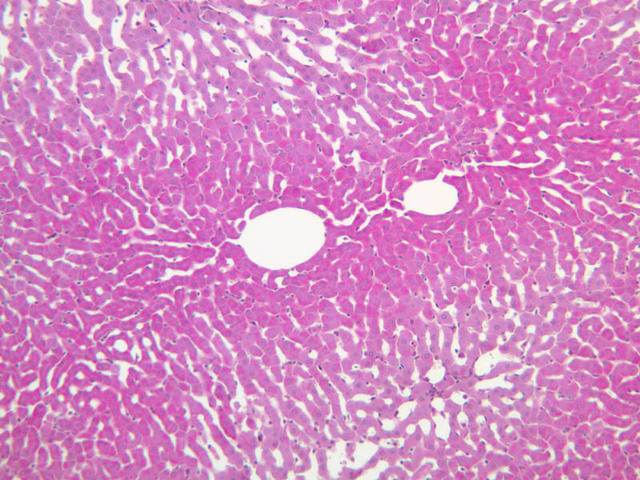

The structure of sinusoids can be studied in the liver (B-29, H&E [10x, 20x, 40x] [10x-labeled, 20x, 40x-labeled]; B-30, H&E [10x, 20x, 40x]; B-35, PAS [10x, 20x, 40x]) where they occur as endothelial tubes between plates of hepatocytes. In the liver, they are channels slightly larger in diameter than red blood cells and the individual lining cells have open spaces between them. The principal difference between sinusoids and capillaries is size, which presumably allows blood to flow more slowly in the larger sinusoids.